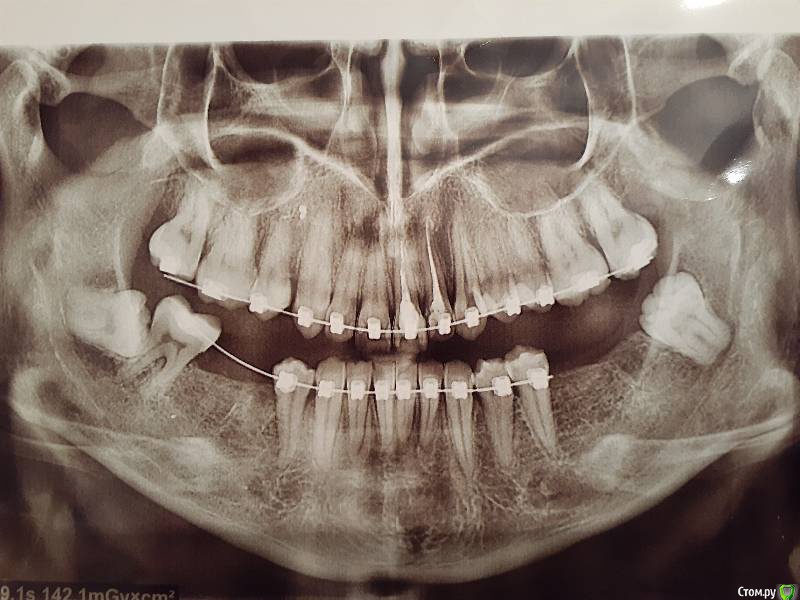

Sheprhan Опубликовано 12 марта, 2020 Поделиться Опубликовано 12 марта, 2020 Добрый день. Подскажите, пожалуйста как быть- у меня установлены брекеты уже год и 8 мес, зубы почти выпрямления,но прикус глубокий дистальный еще не исправлен. На нижней челюсти нет жевательных зубов с обеих сторон. Ортодонт говорит пойти к имплантологу, чтобы уже установили импланты ,мол мне нужна опора,чтобы вытянуть нижнюю челюсть и исправить прикус. А имплантолог, вернее имплантологИ в количестве 2 штук говорят,что нужно пока все лечение ортодонта закончить ,включая исправление прикуса и только потом установкой имплантов заниматься. У меня просьба,пожалуйста, подскажите что мне делать и кого слушать Ссылка на комментарий

Sheprhan Опубликовано 13 марта, 2020 Автор Поделиться Опубликовано 13 марта, 2020 Перед началом ортодонтии была ли консультация стоматолога ортопеда с диагностикой и составлением плана лечения? Или все планирует только ортодонт???на снимке единственное зуб мудрости справа есть,а в жизни я его уже удалила. Есть диск кт,но я с него не понимаю как что-то извлечь. У ортопеды не была((( Ссылка на комментарий